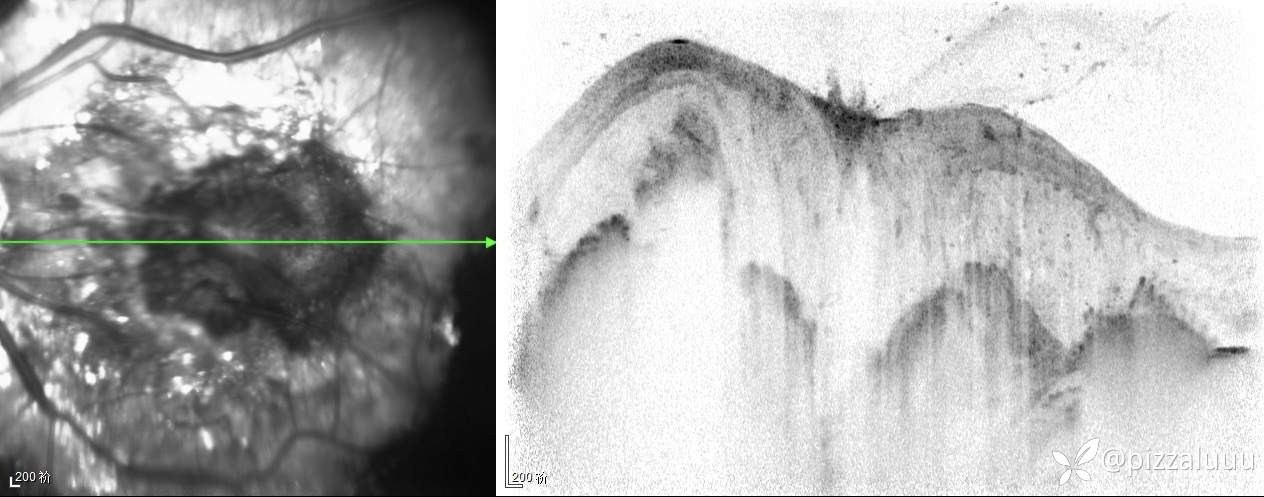

左眼轻度外斜,各位老师考虑这是什么病变?今天只做了这两项检查

玻璃体清,后极部球壁局限隆起,表面粗糙,其内回声不均